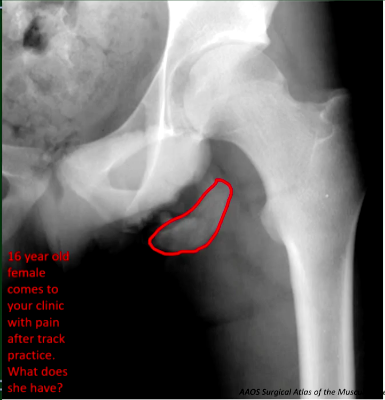

Evulsion fracture at the ischium would injure what muscle?

Hamstrings